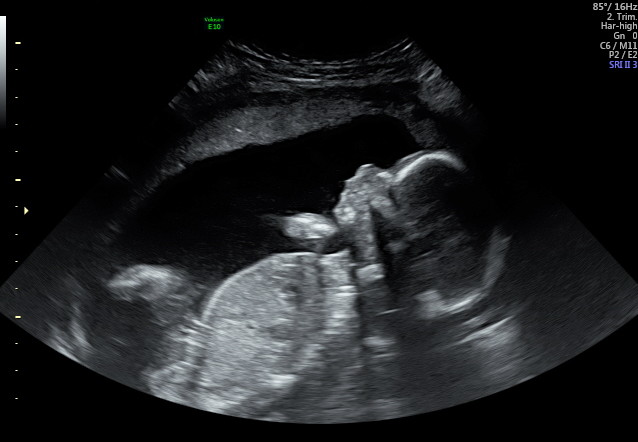

Hell All, as a soon to be first time dad, I've spent hours looking at the ultrasounds trying to determine the gender or the baby.

Because of this we don't have a 'clear' potty shot, but I believe I have found boy bits on 3 other images. I haven't shown my wife this pictures and expressed my guess (nor am I going to) as I know she doesn't want to know,

I'm interested in seeing if my uneducated guess is correct?

don't really have a preference being first child, I think that image on the left is quite clear though? it outlines penis and two obvious 'circles' with 'cords' attached?? what makes you suggest girl?

Because, of the three lines. Could definitely be wrong though. Others will chime in soon that are really good with genders.

I'm leaning toward girl on this one. The potty shot shows 3 lines, although potty shots are not as accurate at this gestation.

I too am leaning more girl than boy but am no expert 😆